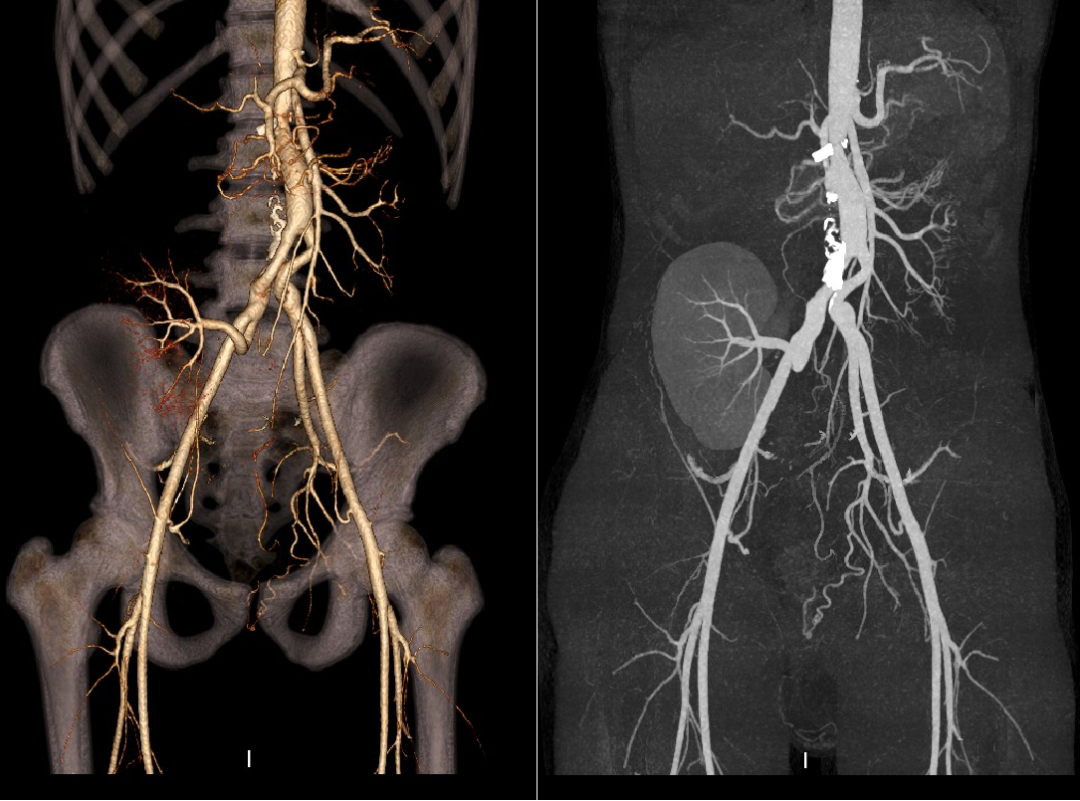

肾周型腹主动脉瘤(瘤体累及双侧肾动脉)

男性,46岁

瘤体起于肠系膜上动脉开口下方,双侧肾动脉开口于瘤体

拟行双肾自体移植:右肾血管严重变异,无法重建,仅行左肾移植